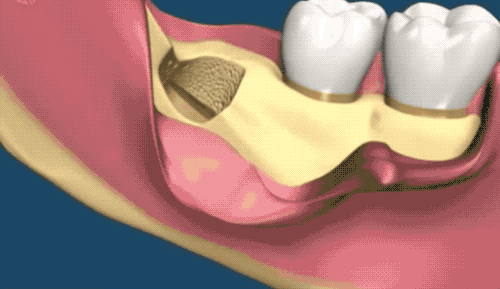

接著介紹下小編的牙齒類(lèi)型,堪稱(chēng) hard 模式的橫阻生智齒。一般生長(zhǎng)情況也分兩種,一種是已經(jīng)出肉的,一種是還未出肉的,操作都差不多,我們就直接看下圖的介紹了。

露出牙槽骨后,先削除一部分骨頭,露出躺臥如睡美人的橫阻生智齒...如果是已經(jīng)出肉的智齒,就沒(méi)這一步了。

請(qǐng)出那令人聞聲喪膽的牙科渦輪機(jī),先分割智齒,撬出塊頭過(guò)大的牙冠來(lái)...再把牙根磨切兩半,依次撬出來(lái)。當(dāng)然這樣的操作并不都是必須的,牙醫(yī)會(huì)依據(jù)當(dāng)時(shí)的可操作性去處理,畢竟每個(gè)哈姆雷特的橫阻生智齒也都可能長(zhǎng)得不一樣。